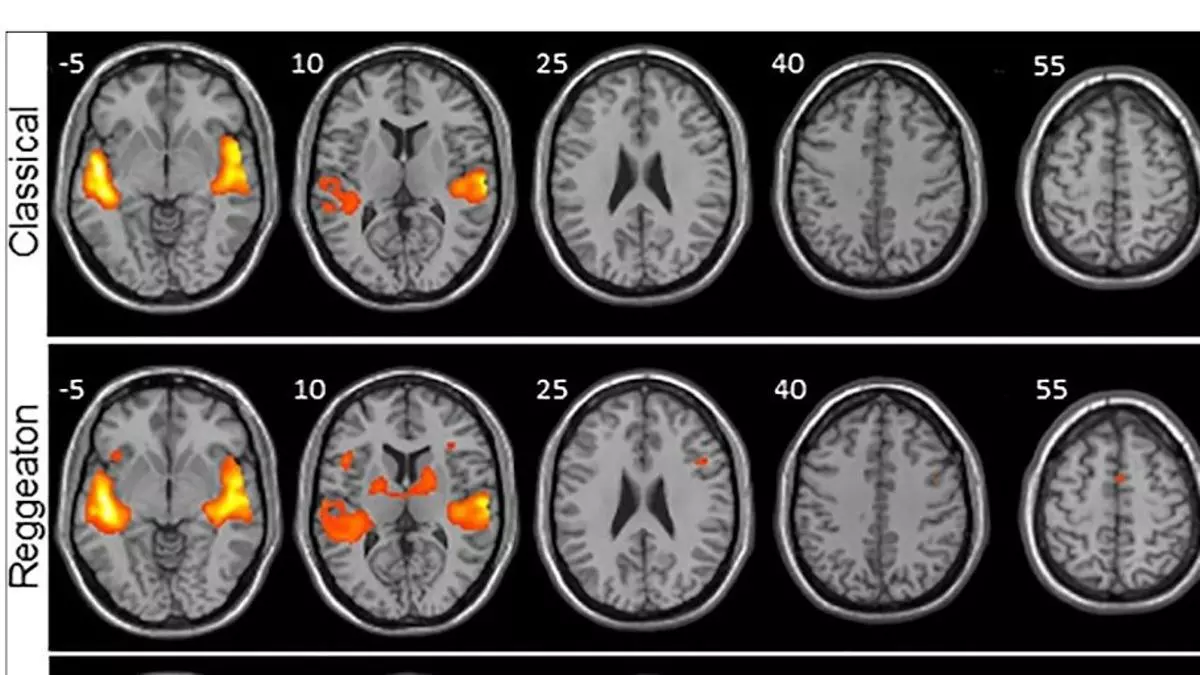

El reguetón provoca mayor actividad cerebral que escuchar clásica o folclore / J. MARTÍN-FERNÁNDEZ / EFE

Frente a la música clásica, el folclore y la electrónica, el reguetón provoca una mayor activación en las regiones del cerebro encargadas de procesar no solo los sonidos, sino también el movimiento, según un estudio llevado a cabo por investigadores canarios sobre la actividad cerebral que produce escuchar diferentes estilos musicales.

Los investigadores analizaron por un lado anatómicamente el cerebro de cada participante y luego la señal BOLD, que consiste en ver qué áreas del cerebro reclutan oxígeno (que es lo que sucede cuando se activan) y a través de un 'software' se representaron con diferentes colores según se activasen más o menos.

Y fue el reguetón el que mostró mayor activación en las regiones del cerebro encargadas de procesar los sonidos (áreas auditivas) y de procesar el movimiento (áreas motoras), unas diferencias que resultaron mayores cuando se comparaban con la música clásica.

La electrónica también mostró una mayor activación de las regiones motoras, pero significativamente menor en comparación con el reguetón. "Lo que más nos llamó la atención fue la activación de una región primitiva del cerebro: los ganglios basales", añade.

La mayor activación provocada por el reguetón implica que hay más regiones cerebrales auditivas y motoras que se activan y por lo tanto hay una mayor maquinaria trabajando en procesar la música.